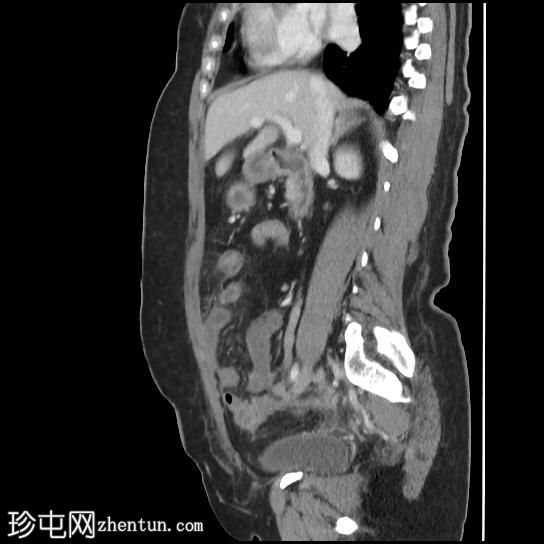

矢状位增强扫描(门静脉期)

矢状位肾盂排泄期

CT扫描显示:

左侧膀胱后外侧壁完全撕裂,造影剂外渗至盆腔

盆腔内可见少量积液

腹膜脂肪条索状改变,腹膜反折增厚强化,提示盆腔腹膜炎

腹腔镜

子宫切除术后医源性膀胱损伤伴盆腔腹膜炎的CT表现。